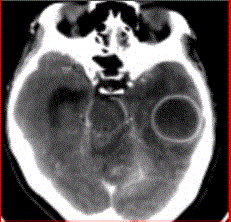

问题 患者女,26岁,头痛、低热10d余,既往有左侧慢性中耳炎病史。CT表现如下图。 关于脑脓肿的诊断要点,不正确的是

选项 A.常合并化脓性脑膜炎 B.颞叶最常见,约占40% C.多发者高达70% D.单发占70% E.病理学和影像学上可分为炎症期和脓肿形成期

答案 C